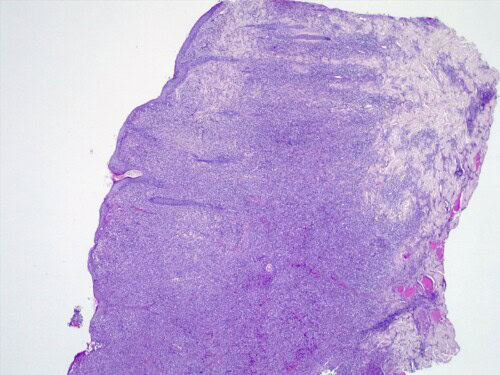

Les résultats d’histopathologie confirment une lésion proliférative tumorale plus qu’inflammatoire, évocatrice d’une histiocytose progressive féline à cellules dendritiques.

Le derme est envahi par une plage cellulaire dense diffus, peuplé majoritairement de cellules rondes indépendantes présentant une allure histiocytaire, des granulocytes neutrophiles et quelques cellules lymphoplasmocytaires.. Elles sont dotées d’un noyau discrètement plicaturé à chromatine à tendance hyperchromatique finement mottée autour de plusieurs nucléoles. Le cytoplasme est abondant acidophile et présente des limites imprécises. On observe également une anisocaryose, et parfois des cellules plurinucléées, et une forte activité mitotique. Les annexes cutanées sont atrophiées et emprisonnées au sein de cet infiltrat. Aucun élément figuré pathogène parasitaires ou fongiques n’est visible sur la réaction au PAS ni sur les différents de section effectués. L’épiderme est ulcéré et hyperplasique.

L’histopathologie se caractérise par un infiltrat dermique et sous-cutané histiocytaire mal délimité, non-encapsulé. Cet infiltrat se compose de cellules rondes à polygonales à rapport nucléo-cytoplasmique bas, et cytoplasme éosinophilique ou finement granuleux, un noyau ovale ou indenté et chromatine mottée. Un épithéliotropisme – agrégats intra-épidermiques de cellules tumorales – est présent dans une proportion non négligeable , 42% selon la même étude.